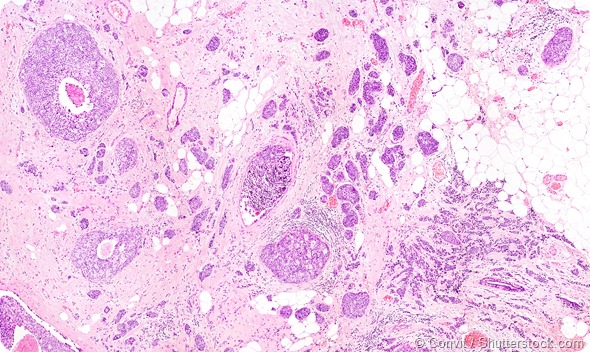

Microscope picture of breast cancer